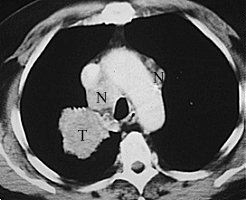

A CAT (Computer Aided Tomograghy) or CT (Computed Tomography) scan uses an x-ray source to measure the non-translucency of the slice of an object. Numerous one-dimensional projections are taken under different angles. From those projections a 2-D intensity distribution is calculated throughout the slice. This results in an image that gives an impression about the inside of an object. The newest types of Spiral CT for medical applications rotate the x-ray source around the patient while the patient is slowly moved through the machine. In 30 seconds, while the patient is holding his breath, a 3-D image of the chest is recorded.

The photo on the right is a regular x-ray photo of a chest with a tumor (T). The photo on the left is a CT scan straight through the tumor, which can now be seen clearly, as well as the metastases (N) next to it.